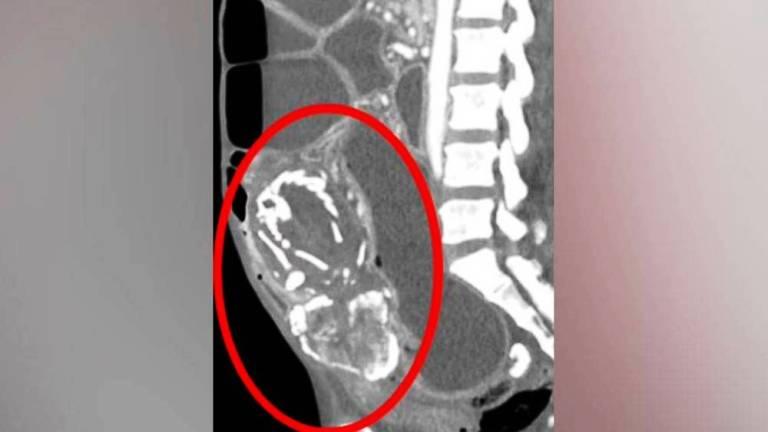

أفريقيا برس – موريتانيا. في حالة نادرة سجلت (300) مرة فقط، فارقت أفريقية الحياة عن عمر ناهز الـ(50) عاماً في نيويورك، نتيجة نقص التغذية الحاد بسبب وجود جنين متحجر في بطنها لمدة (9) سنوات، وذلك بعد (14) شهراً من دخولها الولايات المتحدة متنقلة بين الكونغو وبوروندي ثم تنزانيا بسبب النزاعات السياسية. وأنجت المرأة قبل ذلك (8) أطفال دون وجود أعراض صحية.

وقبل الوفاة بأيام زارت المرأة الطبيب تشكو من عسر هضم، وخلال الفحوص تم اكتشاف وجود جنين متحجر في بطنها، ضغط على أمعائها لفترة طويلة ومنعها من امتصاص الغذاء بشكل جيد ما أدى إلى وفاتها نتيجة نقص التغذية الحاد.

وقال أطباء في مستشفى جامعة ولاية نيويورك وفق صحيفة الخليج: “الخوف منعها من إجراء عملية لتدخل طبي تسبب لها في انسداد الأمعاء المتكرر ترتب عليه سوء التغذية الحاد أدى إلى الوفاة”.